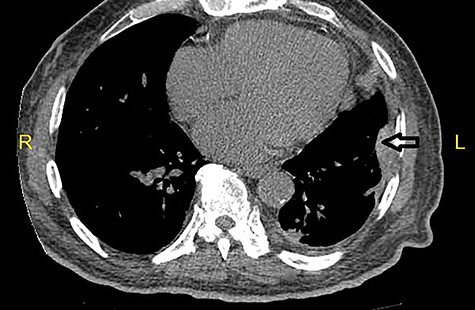

The patient underwent computed tomography (CT) of the chest and abdomen. The CT scan showed nodular thickening of the left lower pleura (Fig. 3). The patient did not return for the scheduled follow-up appointments.

CT scan of the chest reveals nodular thickening (arrow) of left pleura.